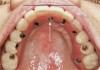

Fig 3. Intraoral occlusal view of a 5-mm diameter dental implant being placed into the nasopalatine canal after enucleation of the contents of the canal. A bone graft was not required because there was no residual gap around the implant. Primary stability was in excess of 40 Ncm insertion torque.

Figure 3